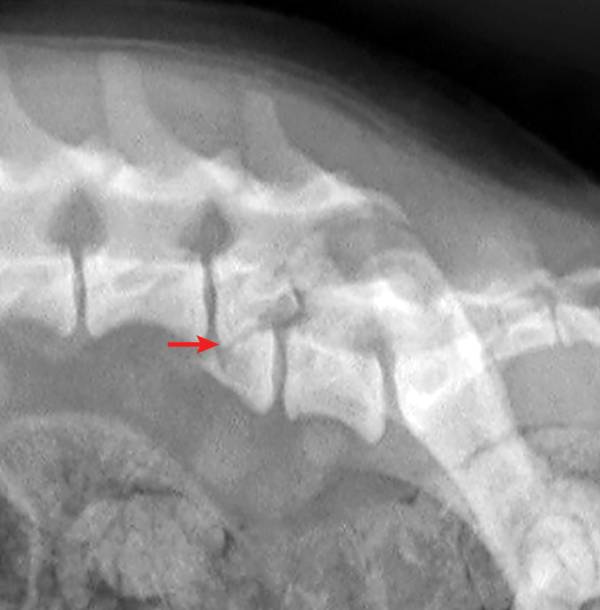

犬猫的椎骨骨折与脱位 宠医客 微信公众号文章阅读 Wemp